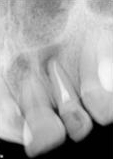

antes depois